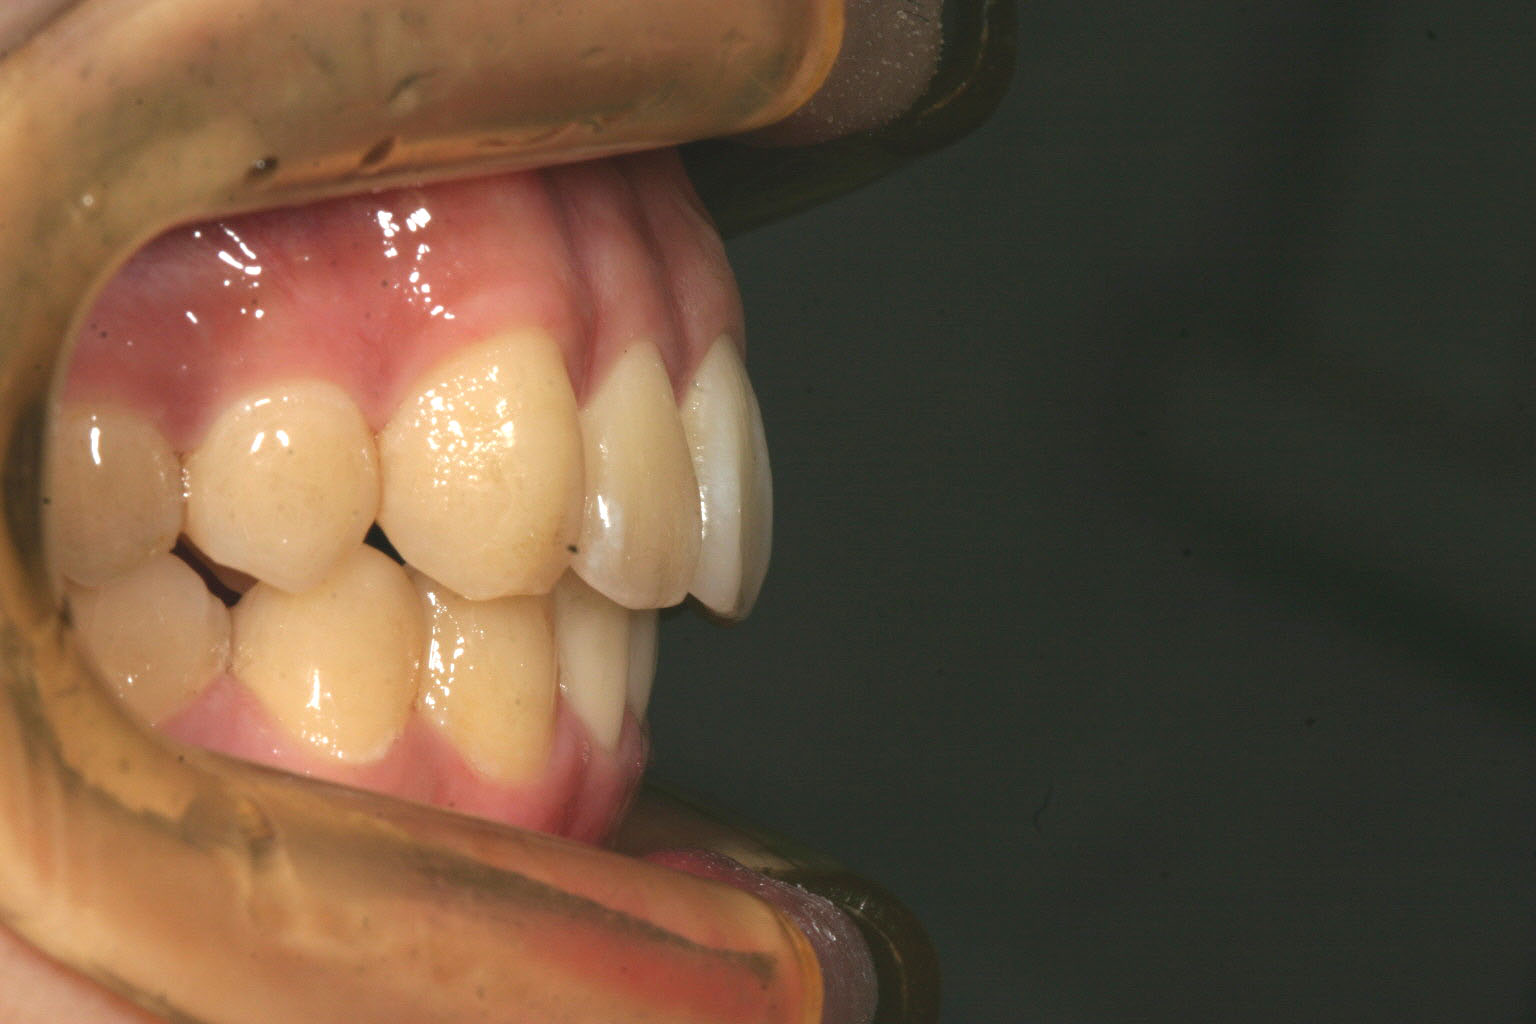

歯列が狭くなっている為前歯が出ています・

下顎も小臼歯部が狭くなり前歯が突出しています。

かなりの前突が見られます。

非抜歯で歯列のを広げました。

下顎も小臼歯部を広げました。

かなり入りました。